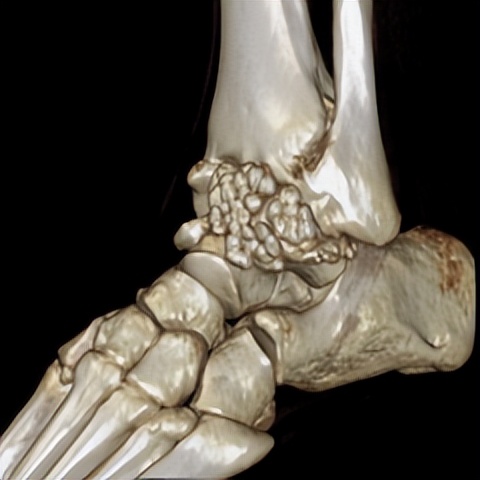

林先生来到省二医后,何河北医生为其进行了详细查体,检查后确诊为踝关节不稳+滑膜软骨瘤

何河北制定了详细的手术方案,为患者开展踝关节镜下滑膜软骨瘤取出术+距腓前韧带重建术。他从患者踝关节中取出32颗“珍珠”(关节游离体),然后进行踝关节外侧韧带重建。

▲术后CT显示滑膜软骨瘤完全取出,韧带重建良好

据何河北医生介绍,对于踝关节损伤,现在最前沿的方法是踝关节镜下修复或者重建距腓前韧带。该技术为全镜下微创,手术时间短,手术创伤小,术后疼痛感较轻,效果良好。